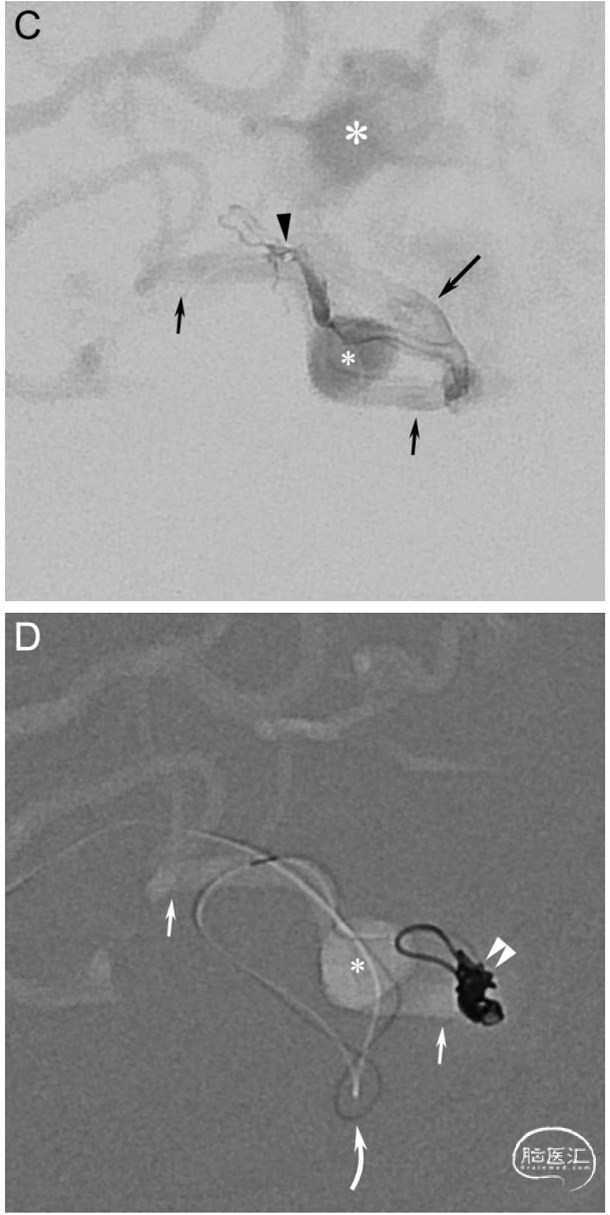

Fig. 2. A 60-year-old man (patient no. 2) presented with left-sided hemianopsia and headache due to an intracerebral hemorrhage in the right occipital lobe. A diagnostic DSA showed a high-grade tentorial DAVF (Borden type III, Cognard type IV). A. Right ECA injection in AP view shows the DAVF supplied mainly by an enlarged middle meningeal artery with arteriovenous shunting to medial (long arrow) and lateral (short arrow) venous drainage routes carrying several ectasias (medial: large asterisk, lateral: small asterisk). Insert: Right ECA injection in lateral view. B. Middle meningeal artery injection in lateral view shows that the main feeder (curved arrow) splits up into smaller pedicles before reaching the venous compartments. The medial venous ectasia (large asterisk) is located above the tentorium, while the lateral venous ectasia (small asterisk) is superimposed by the AV shunt. C. Lateral view of a superselective injection with the microcatheter tip (arrowhead) located distally in the main middle meningeal artery pedicle before entering the venous side. Both the medial (long arrow) and lateral (short arrows) venous drainage routes are visible with their medially (large asterisk) and laterally (small asterisk) located venous ectasias. D. Roadmap in lateral view shows that the 1.3F Headway™ Duo microcatheter (curved arrow) was navigated through the distal pedicle into the lateral draining vein (small arrows) first, where coils (double arrowhead) were deployed. After a minimal pullback and navigation into the opposite direction, coils were also deployed in the medial draining vein. Small asterisk: Venous ectasia on the lateral venous drainage route. E. Volume rendering technique (VRT) reconstruction based on a distal middle meningeal artery injection before coil deployment shows the pedicle (arrowhead) entering the initial venous segment, which divides into medial (long arrow) and lateral (short arrow) draining veins. The course of the microcatheter and the location of the coils are shown. Both the medial (large asterisk) and lateral (small asterisk) venous ectasias are visible. F. Control run in lateral view shows complete blockage of the arteriovenous shunting at the end of the procedure. Insert: Right ECA injection in lateral view shows stable occlusion of the DAVF after 3 months.